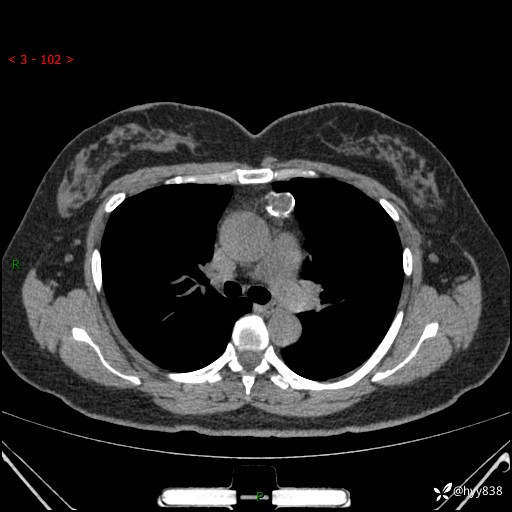

中年女性,检查发现纵隔占位3月余。圆圆的肿物,周围环绕一圈钙化---结果公布~

主诉:检查发现纵隔占位3月余。

现病史:患者于3月前体检行胸部CT检查发现纵隔占位,患者平素无明显咳嗽咳痰,无心慌、胸闷、胸痛、呼吸困难、低热、盗汗,无头痛、头晕,无腹痛、腹胀等不适。现患者欲求进一步治疗,遂来我院就诊,以“纵隔占位”收入我科。 患者自起病以来,精神可,睡眠可,饮食可,大小便正常,体重无明显改变。

胸部CT平扫+增强